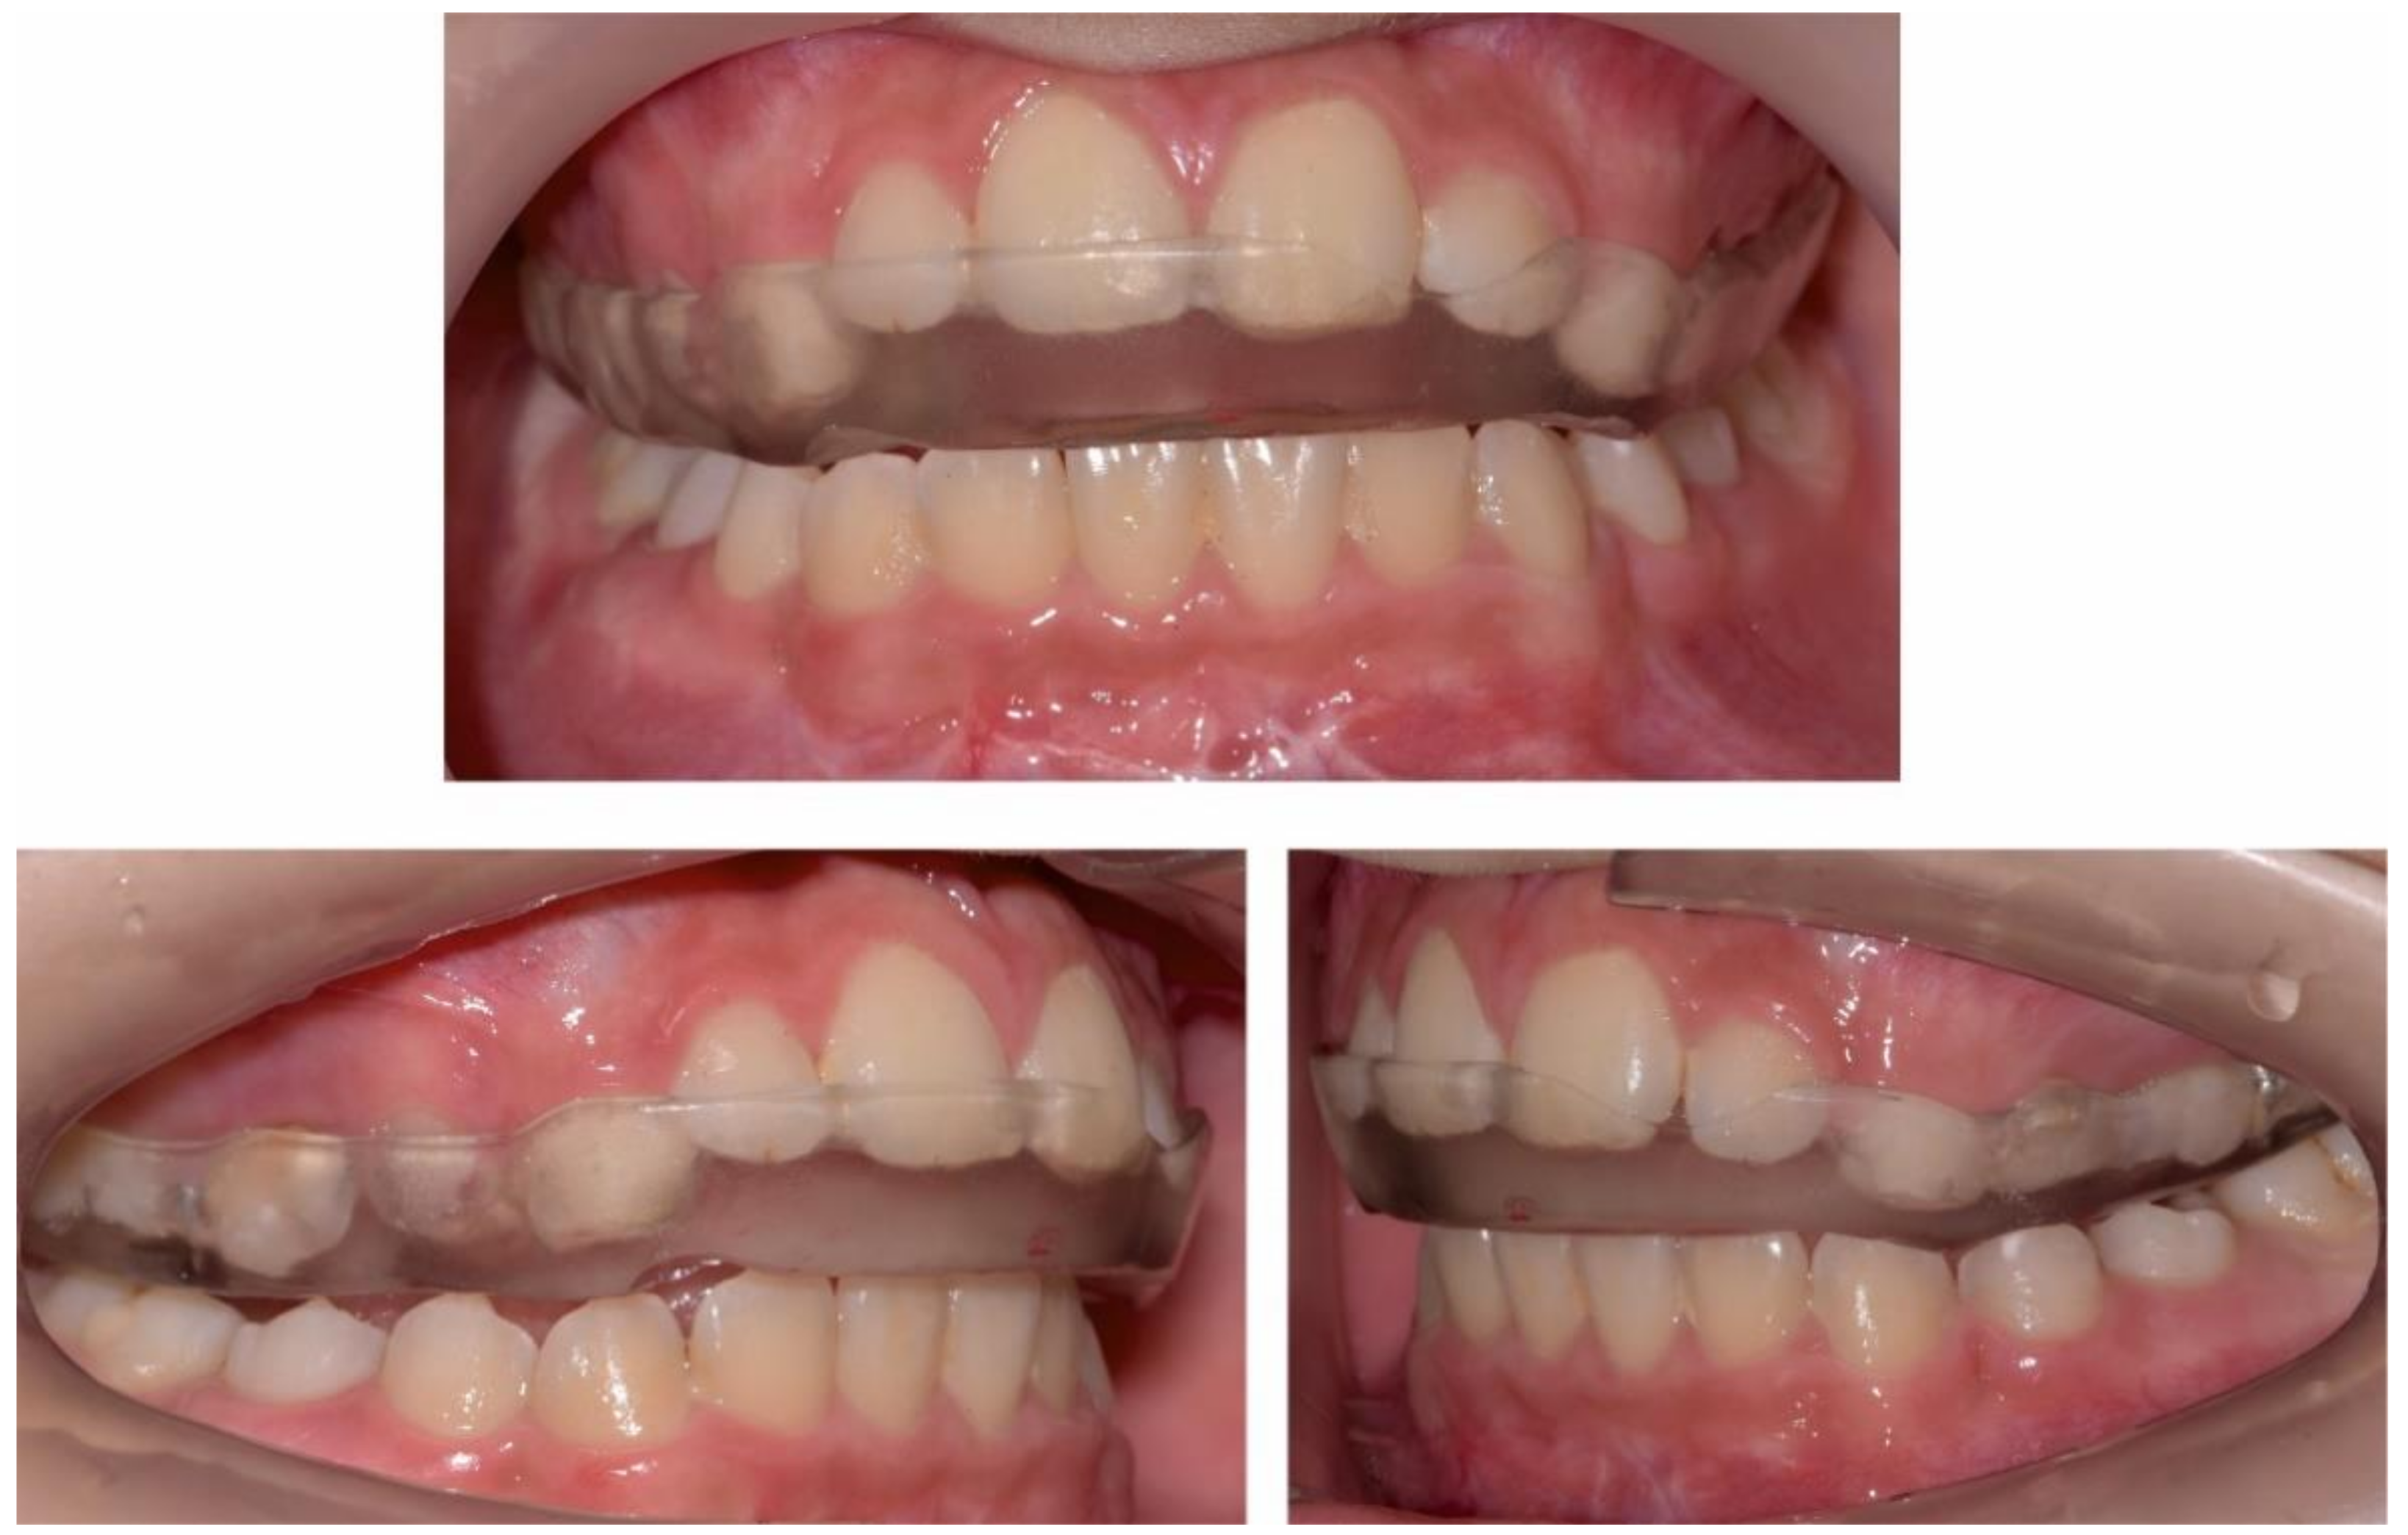

2.2.1. Initial Examination

2.3.1. First Treatment Phase—2016—TMJ Splint Therapy

2.3.2. Second Phase of Treatment—2017—Bite-Blocks and Transpalatal Arch